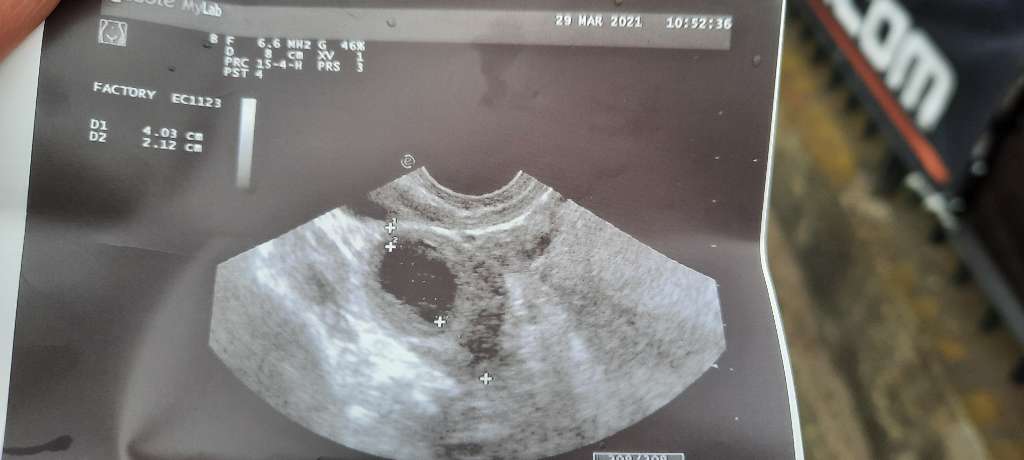

u mnie tak wygląda usg, ja ta widzę jakieś kropki ale nie znam się na tych zdjęciach, no nic trzeba czekac na kolejne usg i mieć nadzieję, że zarodek się pojawi.

• usg.jpg

usg.jpg

1,4 MB · Wyświetleń: 108